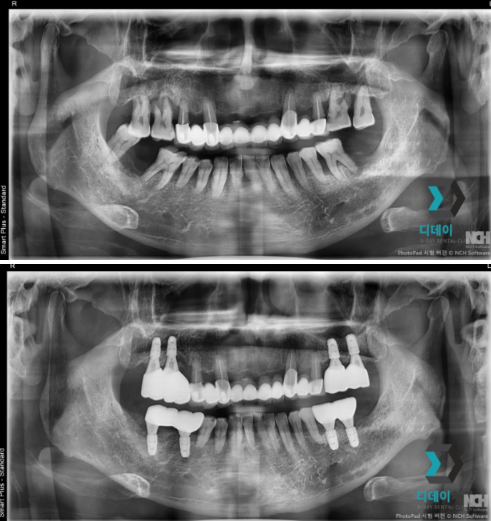

양쪽 위아래 어금니 치주염으로 내원하신 환자분입니다.

양쪽 어금니 심한 치주염으로 인해 발치 후

즉시 임플란트 식립 진행했습니다